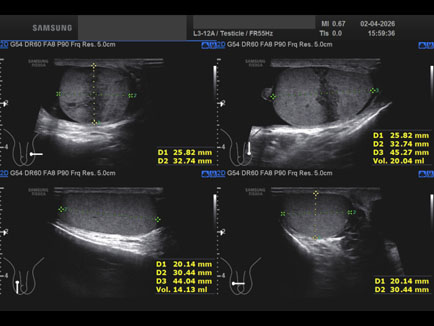

Data inserimento: 07/04/2026

Ecografia del: 02/04/2026

Strumento: Samsung

Sonda: Lineare

Età Paziente: M

Commento all'esame: lesione infartuale del didimo sn dopo intervento per varicocele.

Conclusioni: lesione infartuale del didimo sinistro (Segmental Testicular Infarction - STI).

Realizzazione: Dr. F. Pietro Tarini - Gubbio (PG)

Presentazione: Dr. Massimo Dolciotti - Ancona

Elaborazione digitale: Andrea Dini - Ancona